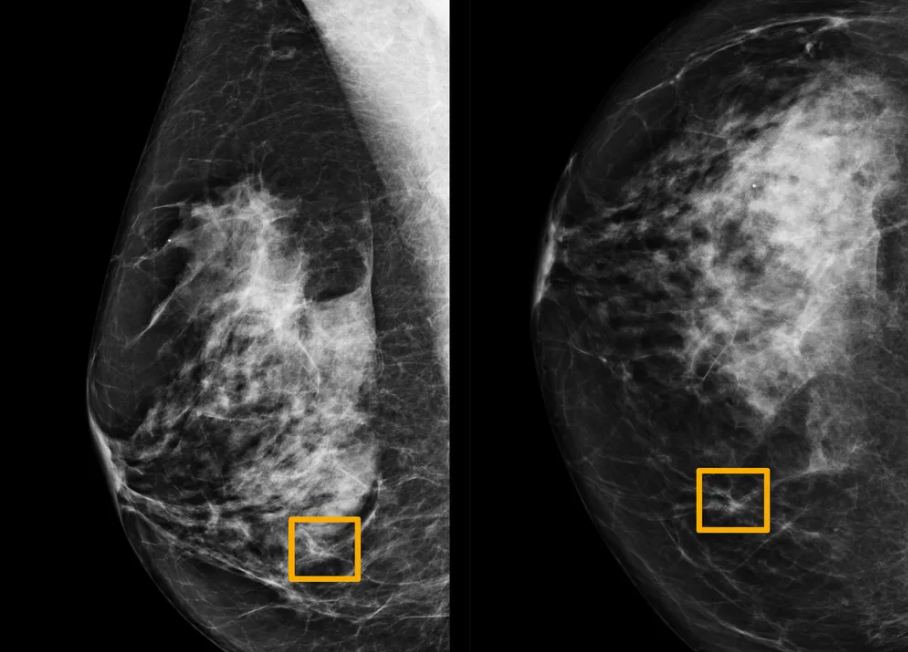

SRM Hackathon 8.0

Finalist in the SRM Hackathon 8.0, hosted by TEAM SRM HACKATHON

April 2024

Project: Lung Cancer Detection Model Using CNN's

- Developed a Deep Ensemble 2D CNN with varied architectures to capture diverse feature representations.

- Combined predictions from multiple CNNs to improve classification accuracy, ensuring robust performance through systematic dataset splitting.